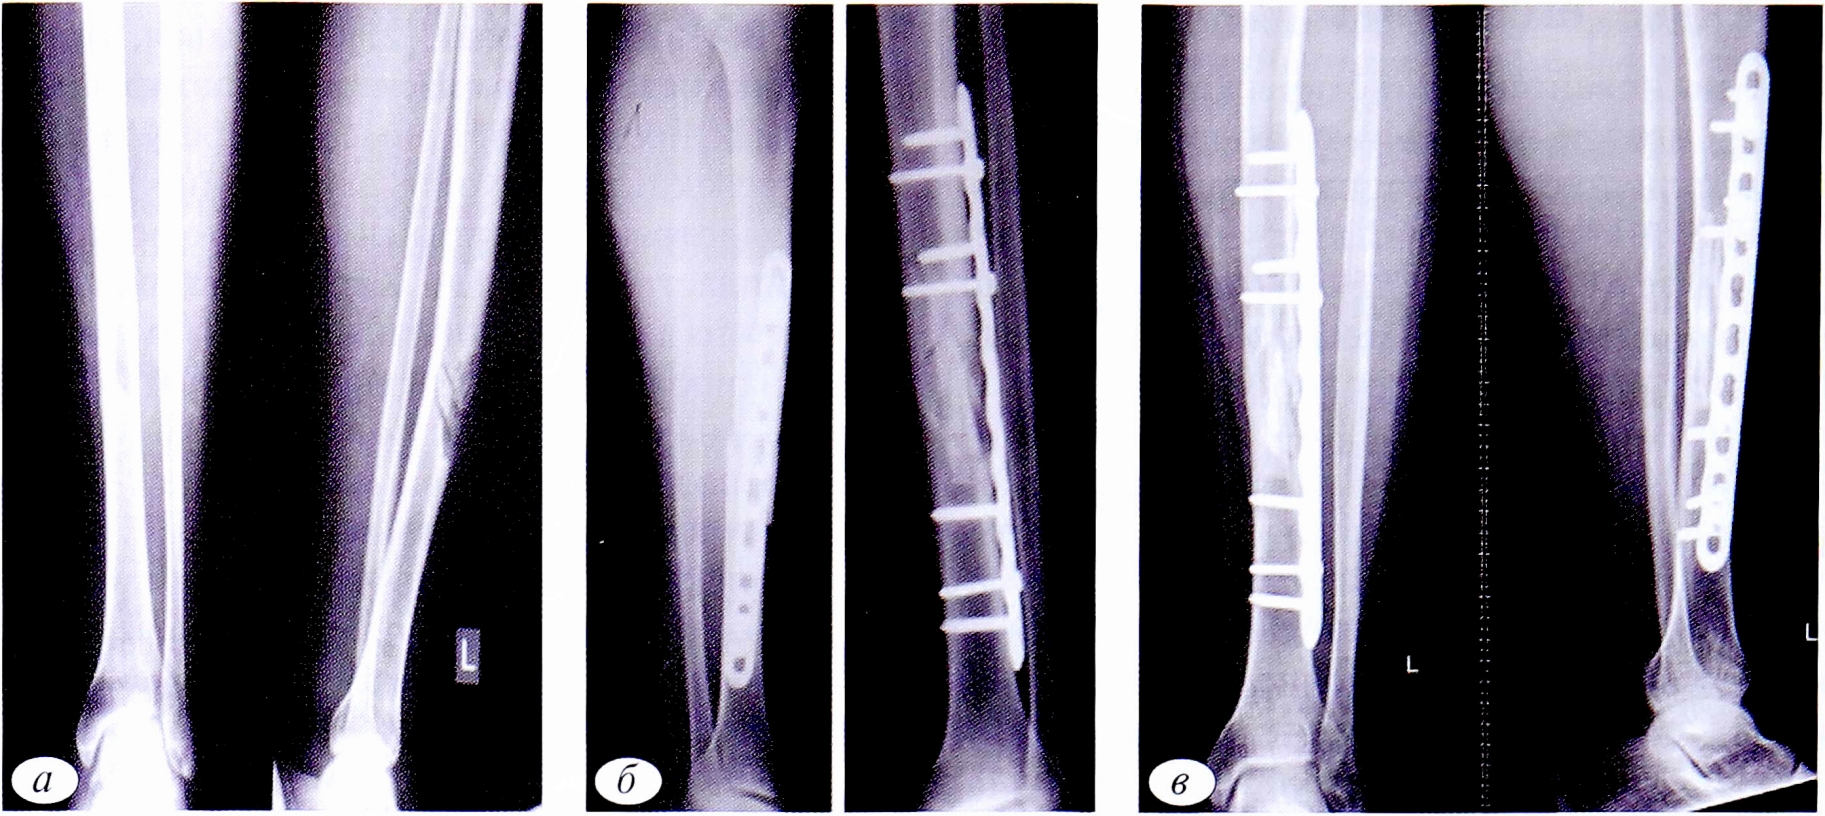

При переломах со смещением (зафиксированы у 19 пациентов), которые возникали в случаях падения пациентов с высоты собственного роста или при прямом ударе в область кисты, после верификации диагноза выполняли оперативное вмешательство: открытую репозицию, краевую резекцию, аллопластику и накостный металлоостеосинтез (рис. 3).

Рис. 3. Пациент К.,18 лет. Диагноз: патологический перелом дистального отдела правой бедренной кости со смещением отломков на фоне аневризмальной кисты. а — рентгенограммы правой бедренной кости в 2 проекциях до операции; б — в 2 проекциях после операции: открытая репозиция, краевая резекция дистального отдела правой бедренной кости, аллопластика ЗКТ, фиксация пластиной и винтами; в — в 2 проекциях через 18 мес: рентгенологически отмечаются консолидация перелома, неорганотипическая перестройка трансплантатов, признаков рецидива заболевания не наблюдается.

Fig. 3. Patient К.,18 years old. Diagnosis: pathological fracture of the distal part of the right femur with displacement of fragments on the basis of aneurysmal cyst. a — radiographs of the right femur in 2 projections before surgery; б — radiographs of the right femur in 2 projections after surgery: open reduction, marginal resection of the distal part of the right femur, alloplasty of the CT, fixation with a plate and screws; в — radiographs of the right femur in 2 projections result after 18 months. X-ray consolidation of the fracture, inorganotypic restructuring of the grafts is noted. There are no signs of relapse.

Патологические переломы при неостеогенных фибромах происходили в 7 случаях, в том числе 4 со смещением,3 без смещения. Они были связаны как с бессимптомным течением самого заболевания, так и с недооценкой угрозы возникновения патологического перелома при ранее выявленном патологическом очаге. В случаях, когда течение заболевания было осложнено патологическим переломом, тактика лечения зависела от наличия смещения костных отломков. При его отсутствии допускалось консервативное лечение гипсовыми повязками. Поскольку сроки сращения патологических переломов при неостеогенных фибромах аналогичны установленным срокам при высокоэнергетических травматических переломах, а патологический очаг оставался в неизмененном виде, то после консолидации перелома выполняли костно-пластическую операцию. При наличии смешения костных отломков применяли открытую репозицию, краевую резекцию, аллопластику и фиксацию перелома пластиной или аппаратом внешней фиксации (рис. 4).

Рис. 4. Пациентка С.,16 лет. Диагноз: патологический перелом нижней трети левой большеберцовой кости на фоне неостеогенной фибромы. а — рентгенограммы костей левой голени в 2 проекциях до операции; б — после операции: открытая репозиция, краевая резекция нижней трети левой большеберцовой кости, аллопластика, металлоостеосинтез.

Fig. 4. Patient S.,16 years old. Diagnosis: pathological fracture of the lower third of the left tibia due to non-osteogenic fibroma. a — radiographs of the bones of the left tibia in 2 projections before surgery; б — radiographs of the bones of the left lower leg after surgery: open reduction, marginal resection of the lower third of the left tibia, alloplasty, metallosteosynthesis.